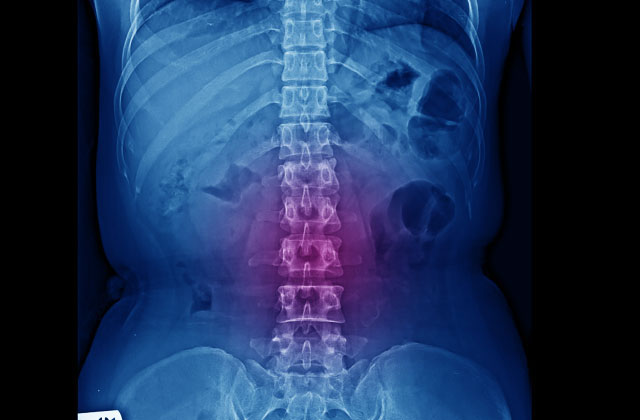

脊柱管狭窄症の原因とは?